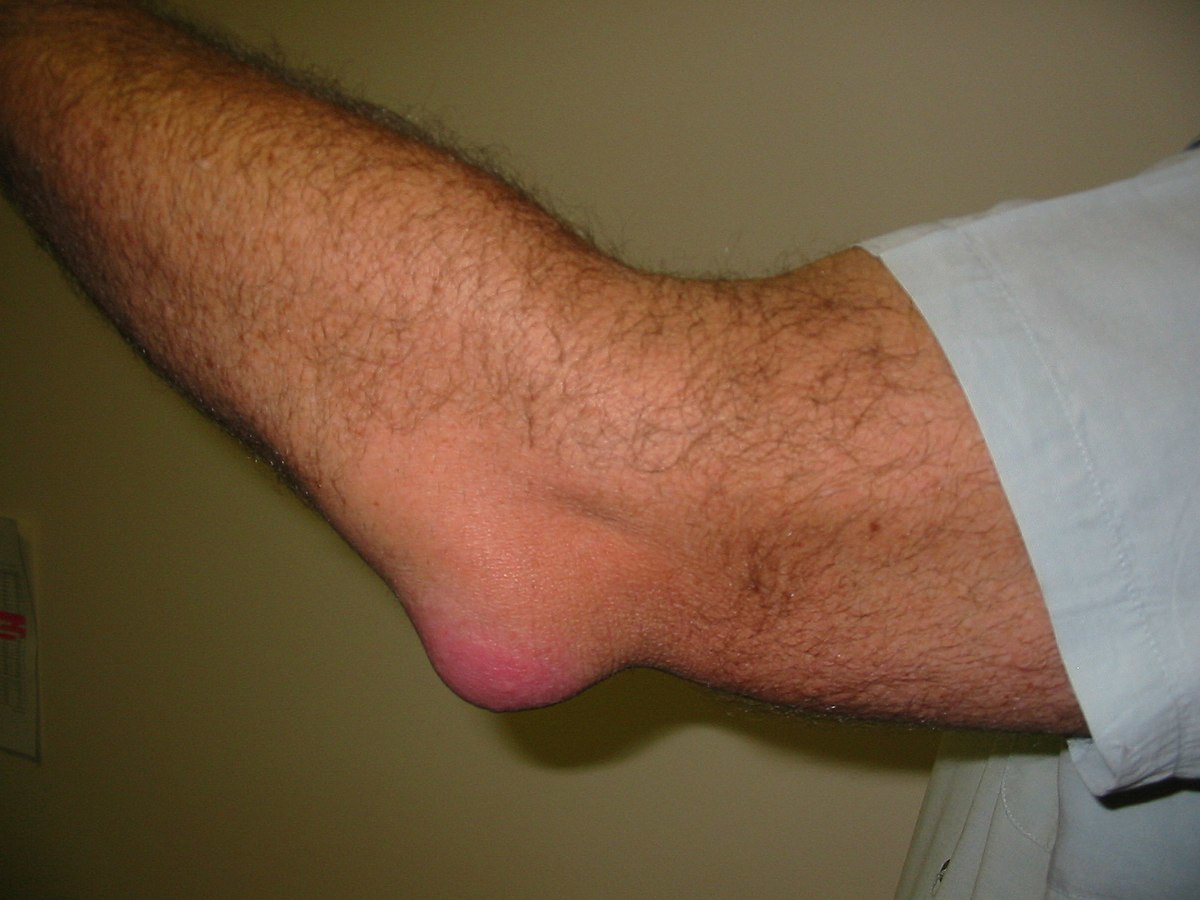

In terms of swellings around the elbow, what is olecranon bursitis?